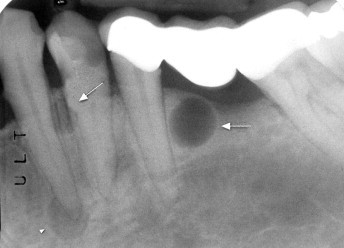

What is this radiolucency?

Stafne defect

*mandibular salivary gland surrounded by madnibular bone*